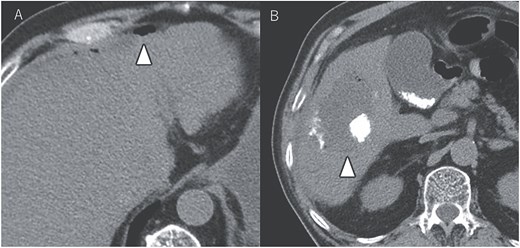

A 72-year-old man presented with abdominal pain. Computed tomography (CT) revealed a liver tumor in segment six/five, abutting the transverse colon without invading. Enlarged lymph nodes in regions 12b and 16b1 were noted, but there were no lung metastases or ascites. Magnetic resonance imaging revealed multiple nodular lesions in liver S6/5 with low signal intensity on T1-weighted images, and mosaic-like high signal intensity on T2-weighted images (Fig. 1). Based on these findings, the diagnosis of HCC was made, staged as cT2N1M1 Stage IVB. The patient underwent transarterial chemoembolization (TACE) followed by ATZ + BV therapy, resulting in tumor and lymph nodes reduction (Fig. 2).

Tumor and enlarged lymph node in region 12b before ATZ + BV (A and B), and which got reduction after chemotherapy (C and D).

CT images showing tumor and enlarged lymph nodes in region 12b before ATZ + BV therapy (A and B). After chemotherapy, reduction of the tumor and lymph nodes is evident (C and D). Notably, no abscess formation was observed in the HCC or surrounding liver tissue, highlighting the direct communication between the tumor and the colon.